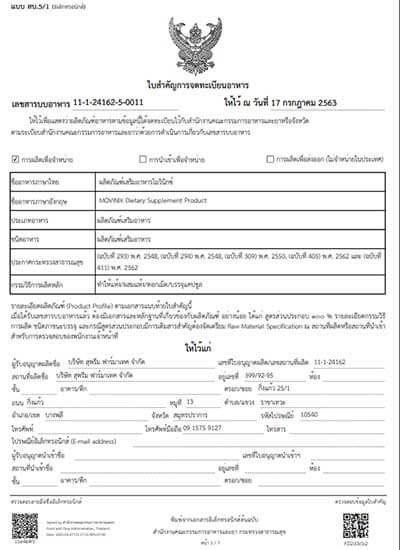

— ใช่ครับ วิธีการตามแนวทางของผมถูกนำไปใช้จริงแล้วอย่างประสบความสำเร็จ ผ่านการวิจัยที่จำเป็นทั้งหมด และได้รับการอนุมัติอย่างเป็นทางการให้ใช้ได้ ผู้ใช้กลุ่มแรกจากประเทศไทยได้ลองใช้วิธีนี้แล้ว ผลลัพธ์ที่ได้น่าประทับใจมาก: ผู้คนมากกว่า 5,000 คนฟื้นฟูสุขภาพข้อต่อได้อย่างสมบูรณ์ ซึ่งคิดเป็น 94% ของผู้ที่ทานแคปซูลจากล็อตแรกทั้งหมด ประมาณ 5.6% พบว่าอาการดีขึ้นอย่างเห็นได้ชัด และมีผู้ใช้เพียง 0.4% เท่านั้นที่ไม่มีการเปลี่ยนแปลงที่สังเกตได้

— ผลิตภัณฑ์ที่เกิดจากการทุ่มเททางการแพทย์ของผมมาหลายสิบปี มีชื่อว่า Movinix มันช่วยกำจัดอาการปวดข้อและไม่สบายตัวได้ภายใน 4 วัน และฟื้นฟูสุขภาพได้ภายในหนึ่งเดือน แม้ในกรณีที่รุนแรงที่สุด

ประสิทธิภาพของ Movinix ได้รับการรับรองด้วยใบรับรองคุณภาพ